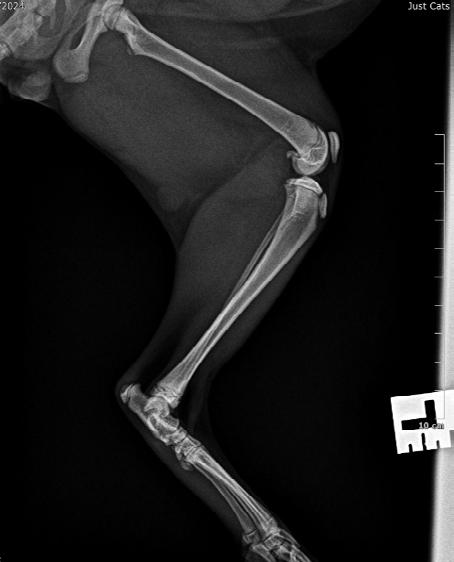

These radiographs are from a 9-month-old cat found by the side of the road ( Figure 1 A&B).

Figure 1. Lateral (A) and DV (B) radiographs from a 9-month-old kitten suspected of having focal osteomyelitis

A. The cat had focal mid diaphyseal osteomyelitis, presumably after penetrating injury, possible after a cat bite wound

B. The cat was started on Amoxyclav (20-25 mg/kg BID), repeat radiographs were planned to monitor the cat’s progress

and lateral (B&C) radiographs from a 9-month-old kitten suspected of having focal osteomyelitis 4 weeks after starting amoxicillin clavulanate

After 4 weeks of Amoxyclav 20-25mg/kg bid (Figure 2 A,B&C) the kitten was clinically normal and non-painful to palpate over the affected area. He was continued on a further 4 weeks of Amoxyclav.

On final recheck and radiograph he was clinically normal and antibiotics were discontinued.